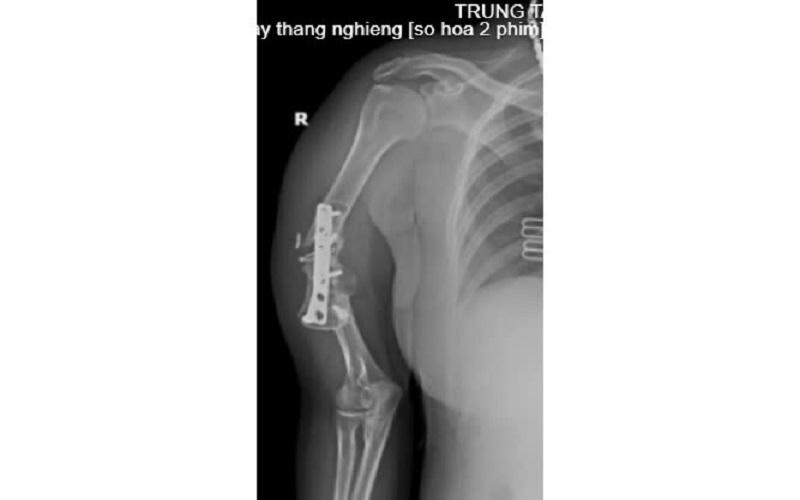

Cách đây 7 năm, sau một tai nạn, chị N.T.L bị gãy xương cánh tay phải, được phẫu thuật kết hợp xương bằng nẹp vít và mang theo phương tiện kết hợp xương kể từ ngày đó.

![]() |

Tình trạng bệnh nhân trước khi mổ. |

Sau khi thực hiện các cận lâm sàng, Bác sĩ kết luận: Khớp giả xương cánh tay phải/Còn phương tiện kết hợp xương, chỉ định phẫu thuật ghép xương điều trị khớp giả.